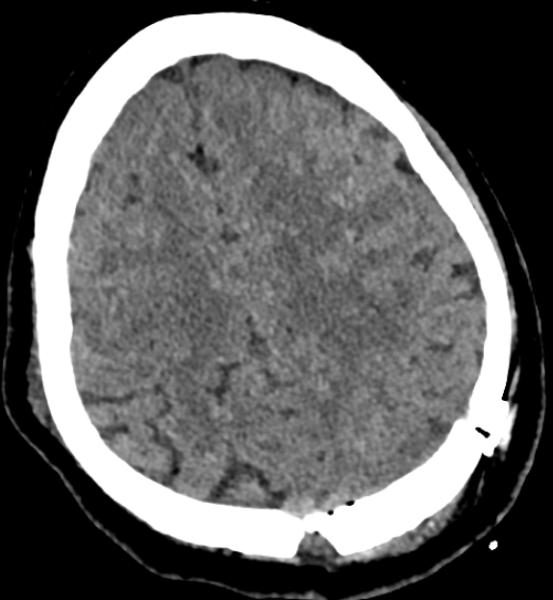

入院后,医院为她进行了详尽的颅脑MRI增强及头颅CT薄扫检查,结果显示其病变位于左侧顶上小叶,病变对脑组织压迫明显(病变周围脑组织CBF灌注明显降低、较对侧脑回体积明显减小),且与左侧大脑上静脉紧密相关,动态视频脑电图分析进一步提示病灶周围脑组织存在异常放电。

术前CT图像

术后复查头部CT显示病变完整切除,脑组织完全复张